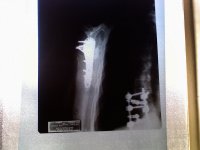

I finally saw an x-ray of the repair job to my right shoulder. The crash happened on 12-29-12. Surgery wasn't untill 1-17-13, and I figure that I've got another month before I can go back to work. I don't know when, or even if I'll be riding again. The doc says that arm will be pretty limited in what it will be able to do. I start PT next week and am looking forward to seeing how quickly the progress comes.

P.S. In the lower right of the pic are parts of the rods for the spinal fusion I had in 2011.